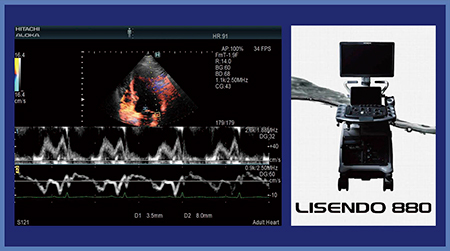

日立製作所製の超音波診断装置には,同一心拍で2か所のドプラ波形を観察可能なアプリケーション“Dual Gate Doppler”が搭載されている。われわれは,2017年5月に販売が開始された同社製循環器用超音波診断装置の新ブランド「LISENDO 880」を使用する機会を得たので,本装置に搭載されたDual Gate Dopplerの有用性と使用経験を報告する。

図1 2か所のドプラ波形を同時に観察可能なアプリケーション

“Dual Gate Doppler”